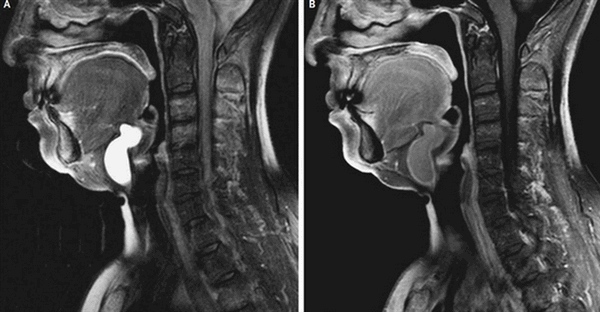

Киста шеи (щитоязычного протока) представлена на двух МР-снимках в разных режимах, имеет гиперинтенсивное содержимое на Т2 ВИ, четкий контур

Сканирование не требует подготовки. Разрешается пить и употреблять пищу. Но переедать не стоит, нахождение в замкнутом пространстве аппарата иногда провоцирует тошноту и рвоту. Стоит отдать предпочтение легкому перекусу, особенно при выполнении томографии с контрастом. Прием пищи позволит уменьшить признаки активности вегетативной нервной системы (тошноту, металлический привкус во рту и т.д.).